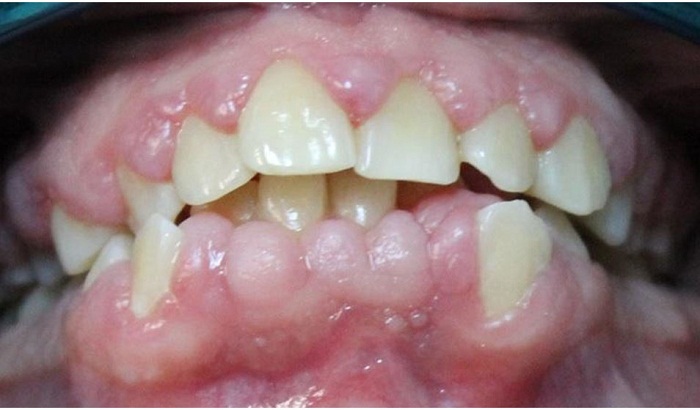

La fase higiénica se inició el 15 de marzo de 2015 y se centró en la motivación en salud oral para lograr un control estricto de placa. Se instruyó a la paciente en el uso de cepillo eléctrico y aditamentos para uso de seda dental, los cuales se sugirieron después de interconsulta con una odontóloga especialista en manejo de pacientes con discapacidad. Los controles de placa mostraron porcentajes del 44,1 %, 37,2 % y 35,8 % durante el entrenamiento en higiene oral. Se realizó raspaje supra y subgingival generalizado y pulido coronal. Al mes, se revaluaron los tejidos y se encontró un mejor índice de placa (22,1 %), así como disminución de la inflamación (figura 3). Se decidió realizar cirugía periodontal bajo sedación con óxido nitroso en la Universidad El Bosque de Bogotá. Se tomaron impresiones de ambos maxilares para colocar placas de presión en acetato de 0,16.